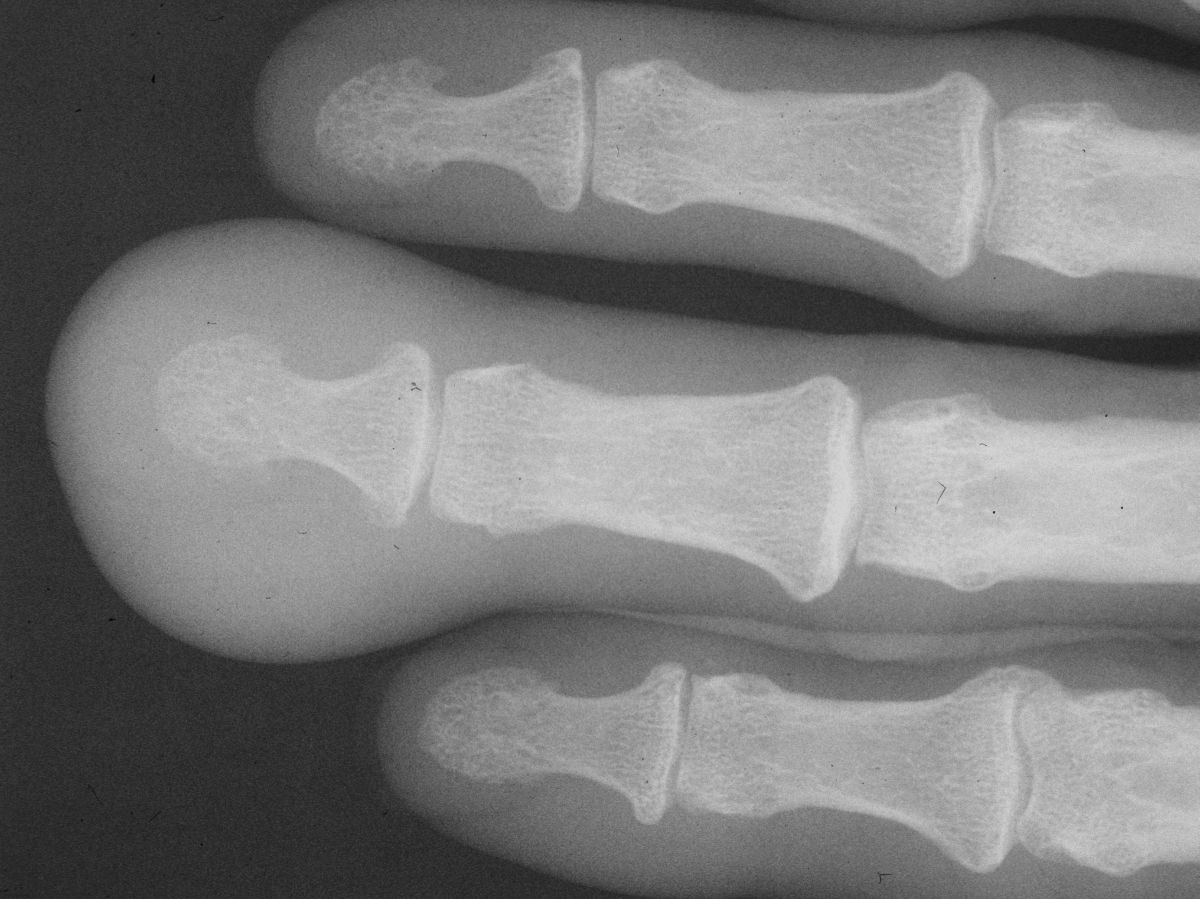

Plain Radiographs demonstrate soft tissue swelling only.